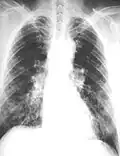

Close-up asbestosis right lower zone ILO 2/2 S/S

Lateral chest X-ray in asbestosis shows plaquing of the diaphragm

The abnormal chest x-ray and its interpretation remain the most important factors in establishing the presence of pulmonary fibrosis.[11] The findings usually appear as small, irregular parenchymal opacities, primarily in the lung bases. Using the ILO Classification system, "s", "t", and/or "u" opacities predominate. CT or high-resolution CT (HRCT) are more sensitive than plain radiography at detecting pulmonary fibrosis (as well as any underlying pleural changes). More than 50% of people affected with asbestosis develop plaques in the parietal pleura, the space between the chest wall and lungs. Once apparent, the radiographic findings in asbestosis may slowly progress or remain static, even in the absence of further asbestos exposure.[26] Rapid progression suggests an alternative diagnosis.